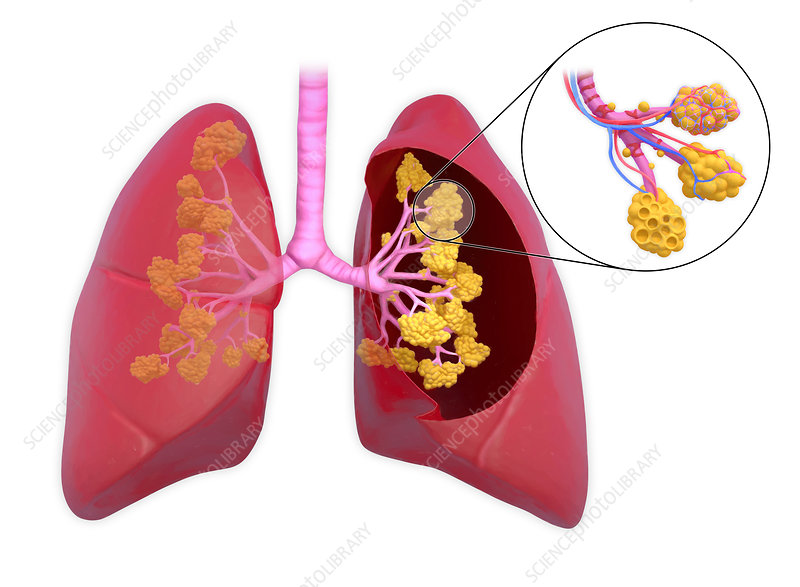

What are alveoli?

Tiny sacs where gas exchange occurs.

What do Type I pneumocytes do?

Gas exchange.

What do Type II pneumocytes do?

Produce surfactant.

What does surfactant do?

Reduces surface tension to prevent alveoli from collapsing.